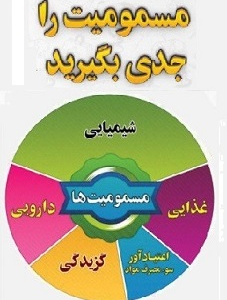

۰۱ آبان ۱۴۰۳هفته پیشگیری از مسمومیت

۰۱ آبان ۱۴۰۳

هفته پیشگیری از مسمومیت

۰۱ آبان ۱۴۰۳هفته پیشگیری از مسمومیت از 1 تا 7 آبان می باشد که در این هفته تمرکز به صورت کشوری، بر ...